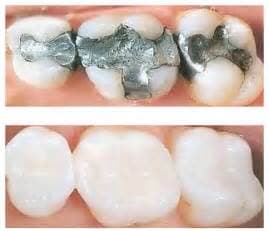

Some people are quite aggressive in clenching their teeth while they sleep and others actually grind them and wear them down. These activities are often associated with jaw joint pain (TMJ) and headaches or migraines. It can also lead to cracked or broken teeth as well as your teeth becoming loose or cold sensitivity. Most commonly this is treated with a variety of mouth guards or bite adjustments. In some cases, injections are done in the chewing muscles which is used to reduce pain and hyper-activity.